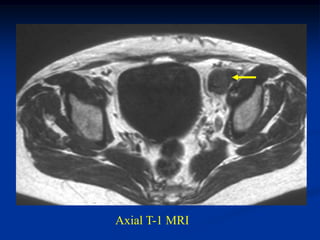

The desmoid tumor does not calcify but is radiodense on ordinary

radiographs and can be easily identified on a soft tissue window CT

scan. The MRI is the best imaging study for this tumor and will be

low signal on the T-1 weighted image but only intermediate high

signal on the T-2 because of the low water content in this tumor

which helps separate it from malignant MFH and fibrosarcoma.

CLASSIC   Case #250.1

Axial T-1 MRI

50 year male with desmoid tumor thigh